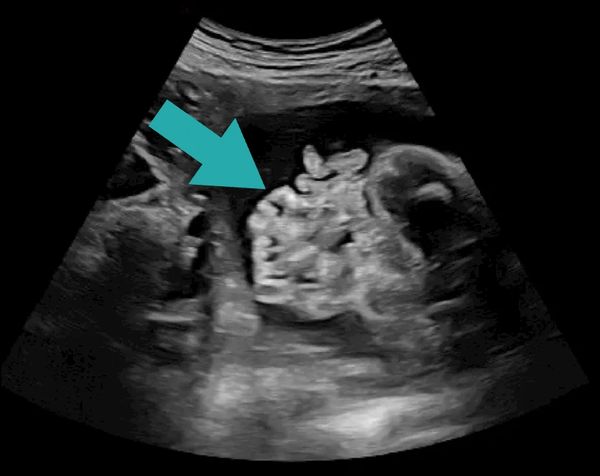

(Pic: fetal ultrasound with arrow demonstrating gastroschisis)

Gastroschisis is a condition where a baby is born with an opening in the abdominal wall, at the umbilicus (belly button), most often to the right of the umbilical cord allowing some of their belly organs (like intestines) to stick out without a covering into the amniotic fluid.